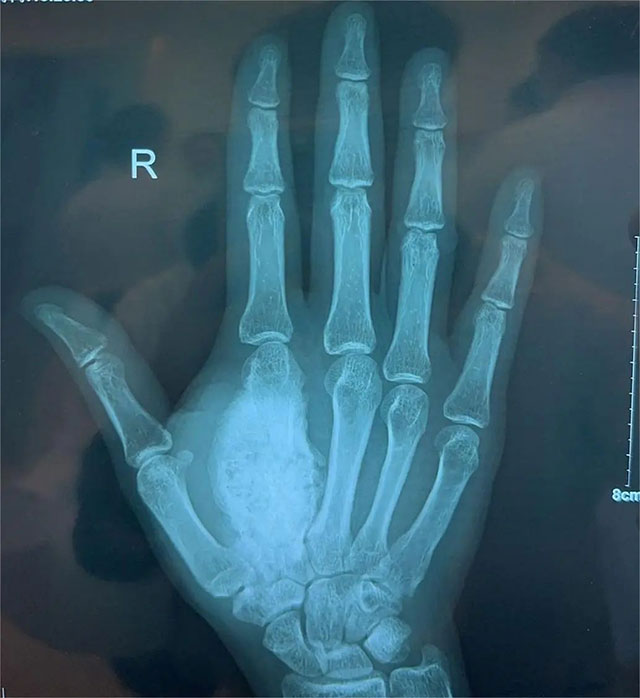

经过查体及影像学检查,可见王星冉右手第二掌骨区域肿块大小约6.5×5×2cm,骨质破坏伴周围软组织肿胀。再进行取活检手术后,初步确定该肿块为骨母细胞瘤。这是一种良性肿瘤,但放任其发展也可能转变性质,而“斩草除根”的办法就是切除肿瘤。

右手正位